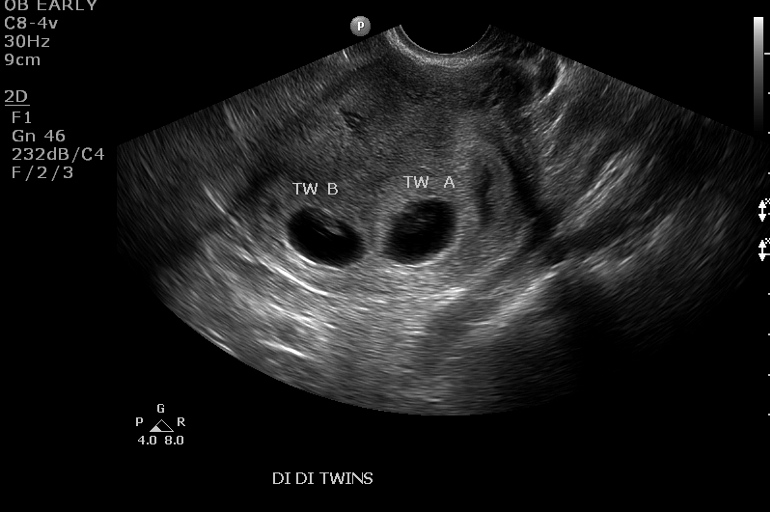

Here's my pic of my twins at 7w. It was super obvious there were two in there (di/di). I know the beans are tiny, but they're there (the tech wasn't the greatest, so the pics we got weren't super clear). Even at the u/s, she was like "here's your baby" then I had to be like "umm, what's that other one?" and she said "that's the other one," so it was clear to me right away. I hope you get some clear answers soon though! Sucks not knowing for sure, but to me it looks like one.

ETA: Of course I JUSt read the update the OP posted! Congrats on the healthy little bean! :)

• Here's my 7w5d u/s and 8w6d two clear sacs and babies...didn't matter how he moved the probe. So I'm inclined to believe you only have one sac, I'm no expert though. Good luck.